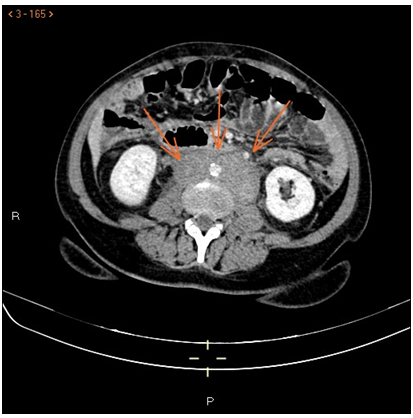

Abdominal CT: a large retroperitoneal mass is observed that involves vascular structures with thickening and hypercaptation of rectum, cecum and terminal ileum walls, as well as multiple inguinal adenopathies, the largest in the left iliac fossa of 26mm.

Figure 2 Axial Scanner Tomography. Retroperitoneal lymph nodes.